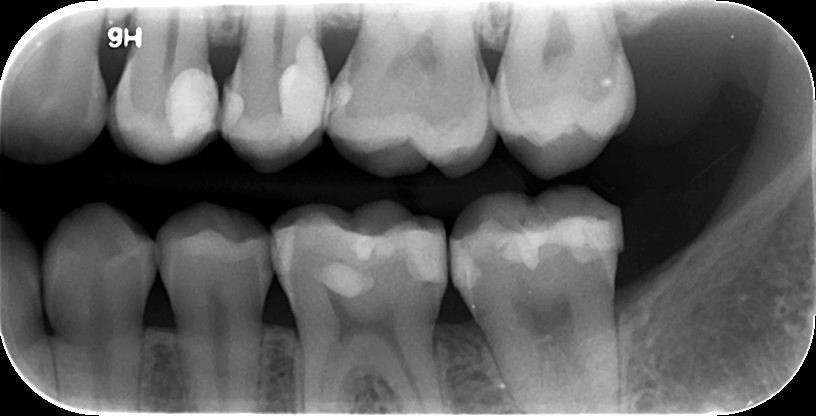

3. ΟΠΙΣΘΟΜΥΛΙΚΗ ΑΚΤΙΝΟΓΡΑΦΙΑ

Με την οπισθομυλική ακτινογραφία επιτυγχάνεται η ταυτόχρονη απεικόνιση των μυλών των άνω και κάτω οπισθίων δοντιών ενός ημιμορίου (μιας πλευράς) με μία λήψη. Λαμβάνεται με την τοποθέτηση του ακτινογραφικού πλακιδίου εσωτερικά των δοντιών (προς την πλευρά της γλώσσας και του ουρανίσκου) και παράλληλα με αυτά. Χρησιμοποιείται ειδικός συγκρατητήρας οπισθομυλικών, τον οποίο δαγκώνει ο εξεταζόμενος.

Χρησιμοποιείται για την ανίχνευση τερηδόνων στις μύλες των δοντιών, κυρίως στις όμορες επιφάνειές τους (γειτνιάζουσες επιφάνειες δοντιών).